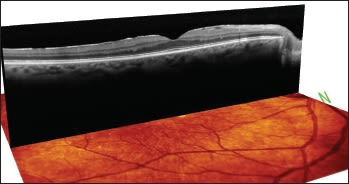

For example, Figure 1 is a 52-year old −4 D myope who had a retinal detachment repair recently with buckle. "The retinal detachment went right up to the edge of the macula and although the macula looks abnormal on exam, the Spectralis shows a rather normal macula architecture in this, his dominant right eye," says Dr. Safran. "This patient did extremely well with Crystalens in this eye, ending up 20/20 and J2 uncorrected."

"The next patient (Figure 2) also had Crystalens surgery in the dominant eye and did very well despite the presence of epiretinal membrane (ERM) on exam," he notes. "The OCT shows normal macula architecture, which indicates that, despite the ERM, the patient should do very well without problems."

Figure 2. This patient had an ERM, but the image shows normal macular architecture, which allowed Dr. Safran to successfully implant the Crystalens without need for a retina referral.